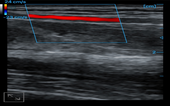

Carotid + CF + PW + Auto Trace

Carotid + CF + PW + Auto Trace